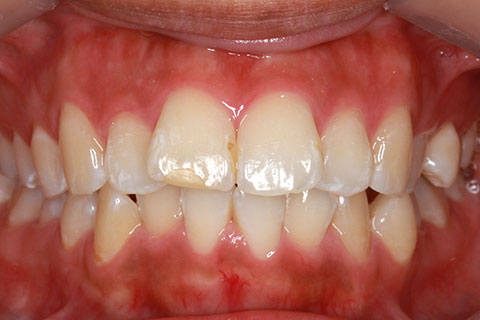

ハーフリンガル矯正4(上の歯のみ舌側矯正で治療)

治療前

治療中

治療後

- 年齢・性別

- 23歳女性

- 治療期間

- 2年0ヶ月

- 抜歯

- 上下4番抜歯

- 治療費

- 110万円

- マルチブラケットを用いた矯正治療

- 治療内容

- 施術の副作用(リスク)

- 表側矯正と比較して、前歯のラビッティング(舌側傾斜)を起こしやすい。